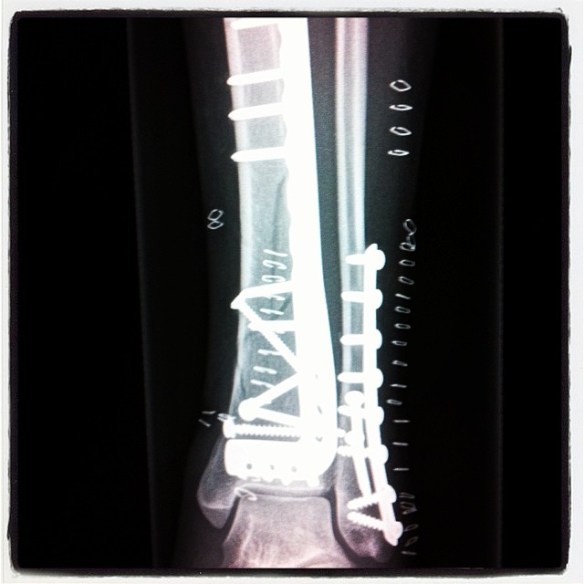

Her most recent trip was an enviable journey from Canada to Panama and back up to El Salvador, hunting for tubes in their beloved van Ezmerelda. Their trip was cut painfully short when Carmen shattered her ankle during a magic session at one of El Salvador’s most famous waves. Breaking all three bones in five different places, followed by three sleepless nights in the van, she was finally rewarded with an excruciating plane ride home and fixed up with two large plates and 23 screws. Ouch!

After a three hour wait for X-Rays they told me both my leg bones where broken and that if I stood on it the bones would pierce the skin. I was sent on my way with an air cast that was too big, with no air in it, that pretty much did nothing! I could feel the bones moving and grinding. Nasty! I “slept” in our van for three nights before flying back to Canada, abandoning Ezmerelda, our beloved van. Two flights with incredibly painful wheelchair service then straight to a wonderful clean Canadian hospital. More X-Rays, showing five breaks not two. Three more days waiting for surgery before being released with one 7-inch long L plate on my Tibia, one medium size plate on the Fibula and 23 screws! Lasted an hour at home before returning to hospital due to complications. Spent another week there on bed rest, so drugged out on morphine I couldn’t even breath anymore. I’m so lucky I had Rick to do EVERYTHING for me!